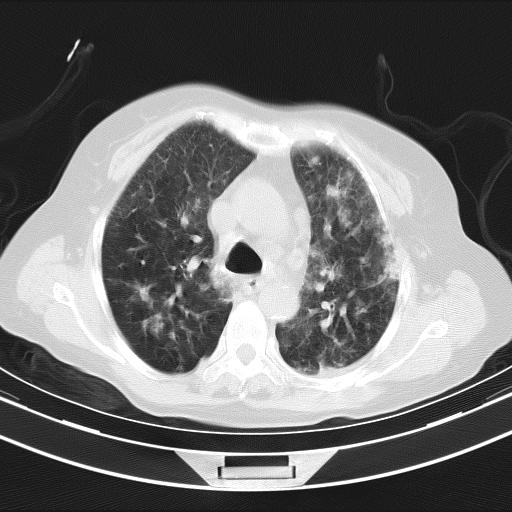

老年女性,嗜睡3天,意识模糊。轻咳,无发热。

双肺多发淡片影,毛玻璃影,,支持支气管肺炎,,建议血气找原因,,嗜睡是否肺性脑病?有没有慢支病史?

甲流?

双肺炎症,建议抗炎治疗后复查,见过几个老年肺炎病例,没有发烧、咳嗽症状,直接以昏迷就诊。

1)两肺感染性病变;建议抗炎治疗后复查。2)纵隔淋巴结肿大。3)左侧胸腔积液。

1)先考虑两肺感染性病变;建议抗炎治疗后复查。

2)纵隔淋巴结肿大。

3)左侧胸腔积液。